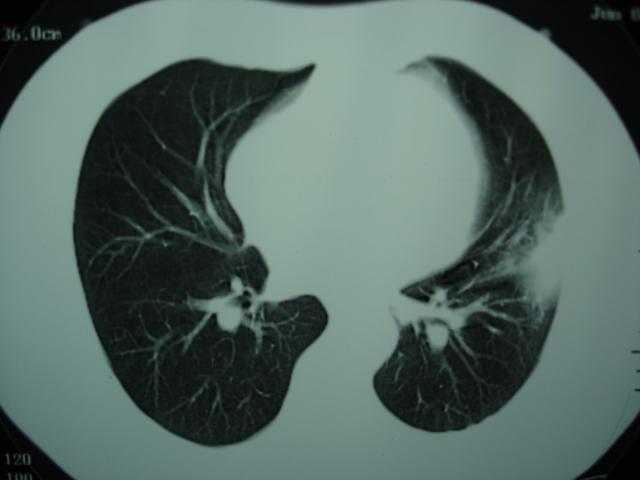

第三次ct2009.8.21

考虑 左肺上叶炎症感染 [炎性假瘤可能性大]。

不排除肺癌

考虑左肺上叶炎症感染,以炎性假瘤可能性大。